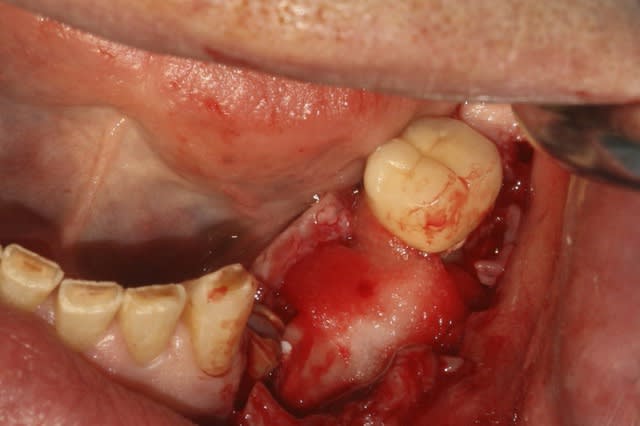

image1: incision verticale + décollement du lambeau de proche en proche

image 2: prélèvement Ramique

image 3 et 4: découpe d'une fine lame allant servir de toit

image 5: broyât osseux

image 6: insertion du "toit"

image 7: fixation ( vis Stoma)

image8: ajout du broyât

image 9: sutures